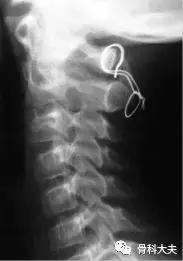

A:几乎所有的急性环枢椎半脱位(Hawkin I型)通过早期的保守治疗,都能够痊愈。针对极少数伴随神经症状或因为治疗延迟导致的保守治疗失败病例,可能需要融合手术治疗。可采用颈椎后路植骨融合+halo背心外固定。后路植骨融合的方法有:Gallie法,该方法简单,辅以Halo背心,融合效果满意;Brooks法,采用两根椎板钢丝,更加稳定,但增加了脊髓损伤的风险。

Gallie法融合

目前,还可采用更加坚强的螺钉作为内固定,主要有两种手术方式:Magerl穿关节螺钉或寰枢椎的钉杆系统内固定。需依据病人的局部解剖情况、医生的习惯来选择具体的手术方式。

C1/2钉杆系统和Magerl螺钉